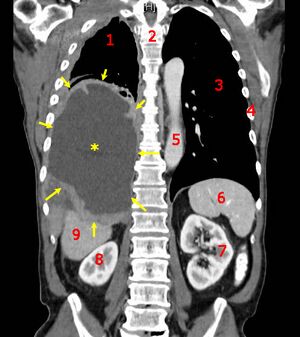

![]() | |

CT scan showing a left sided mesothelioma with an enlarged mediastinal lymph node | |